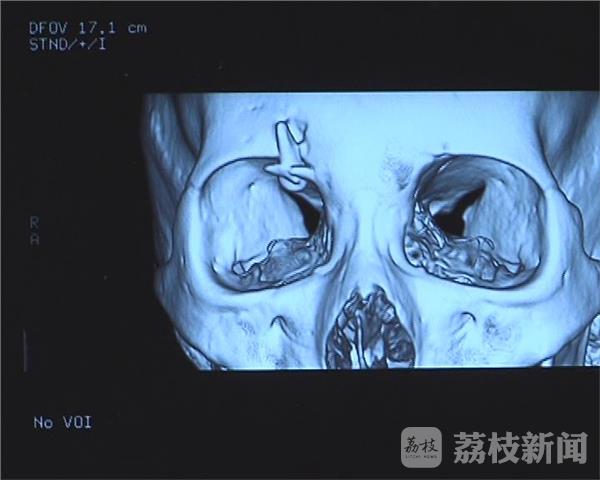

发生车祸后,婷婷的右侧眉骨损伤严重,在当地医院医生进行了缝合清创处理,然而,几个星期过去了,婷婷的右眼开始视力模糊。当婷婷来到省中医院神经外科,医生检查后惊讶地发现,一颗“牙齿”状的异物卡在了婷婷的眉骨上,这颗门牙状的异物已经对婷婷的眼球造成了压迫,影响了婷婷的视觉。

江苏省中医院神经外科医生傅传经说,从片子来看,在婷婷右侧眼眶的上缘,能看到一个类似于牙齿形状的异物,结合对方患者的门牙,高度怀疑异物就是个牙齿。由于牙齿釉质比骨头密度还要高,牙齿前面也是比较锐利的, 如果相撞的时候,正好是锐口对骨头,这个瞬间牙齿是能够将骨头戳穿,卡进入骨头里的。